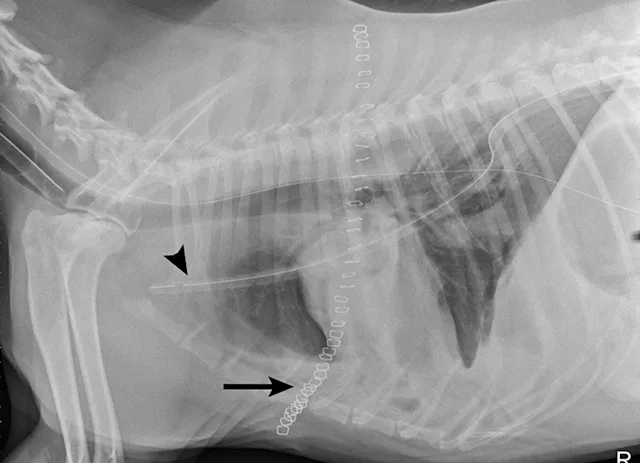

CT demonstrated bilateral moderate pleural effusion with an abnormal appearance of the left cranial lung lobe, stippled gas collections, and truncation of the bronchus that suggested LLT (Figure 4).

Left lateral thoracotomy revealed LLT in the caudal portion of the left cranial lung lobe, and a lung lobectomy was performed. A 20 Fr thoracostomy tube and pleural catheter were placed for postoperative recovery, monitoring, and pain control (Figure 5). Two days postoperation, the amount of pleural effusion aspirated from the thoracostomy tube was still significant in quantity (72 mL/kg/day) and off-white in color (Figure 6). The fluid was confirmed to be chylous effusion based on cytologic examination results (ie, lipid droplets, moderate numbers of mature lymphocytes, and a few macrophages) and paired serum (95 mg/dL) and effusion (819 mg/dL) triglyceride levels.